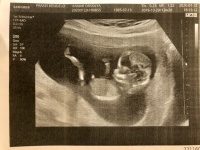

Szegény olyan kis elesett. Egyébként 2 fiam van, a nagyobb 7 éves, a pici 4. Már várom, hogy kiderüljön a harmaik neme is

Ki mikor megy legközelebb dokihoz? Ti akkor mostanság mentek/vagytok túl a 12. heti uh-kon, ugye?